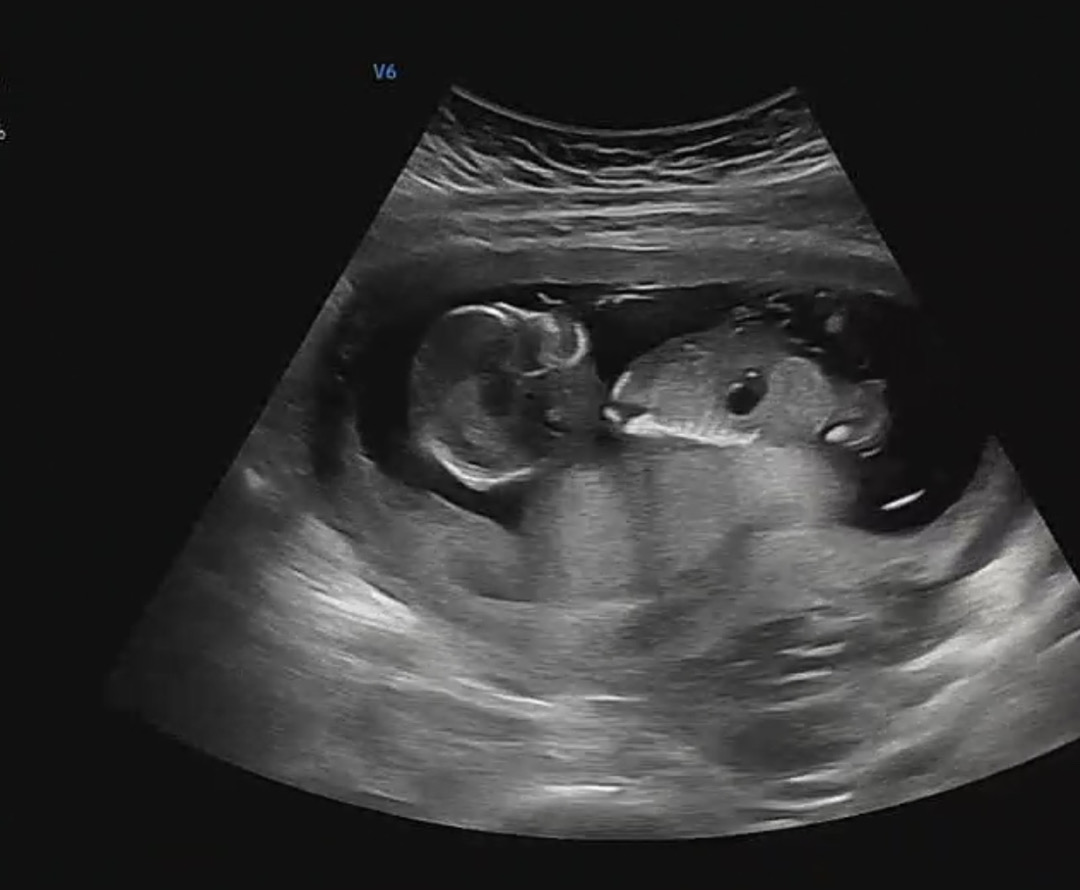

13주 6일차 초음파예요~ 혹시 보이시면 각도법 투표 부탁드려요🤭

13주 6일 각도법 봐주세요 ㅎㅎ